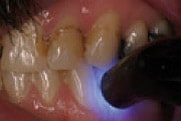

Figure 8

Cementation of Protemp™ Crown Temporization Material in patient’s

mouth using temporary cement.